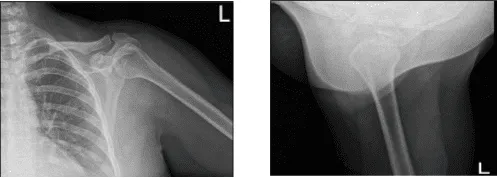

Se revisaron radiografías y se discutió que su hombro izquierdo mostraba radiografías normales. Aconsejamos al paciente que se hiciera una resonancia magnética para ver la causa y descubrimos una rotura de grosor parcial del tendón subescapular, aunque no hay desgarro de alto grado parcial o total del manguito rotador. Presencia de tendinosis supraespinosa e infraespinosa.

Radiografía del hombro izquierdo